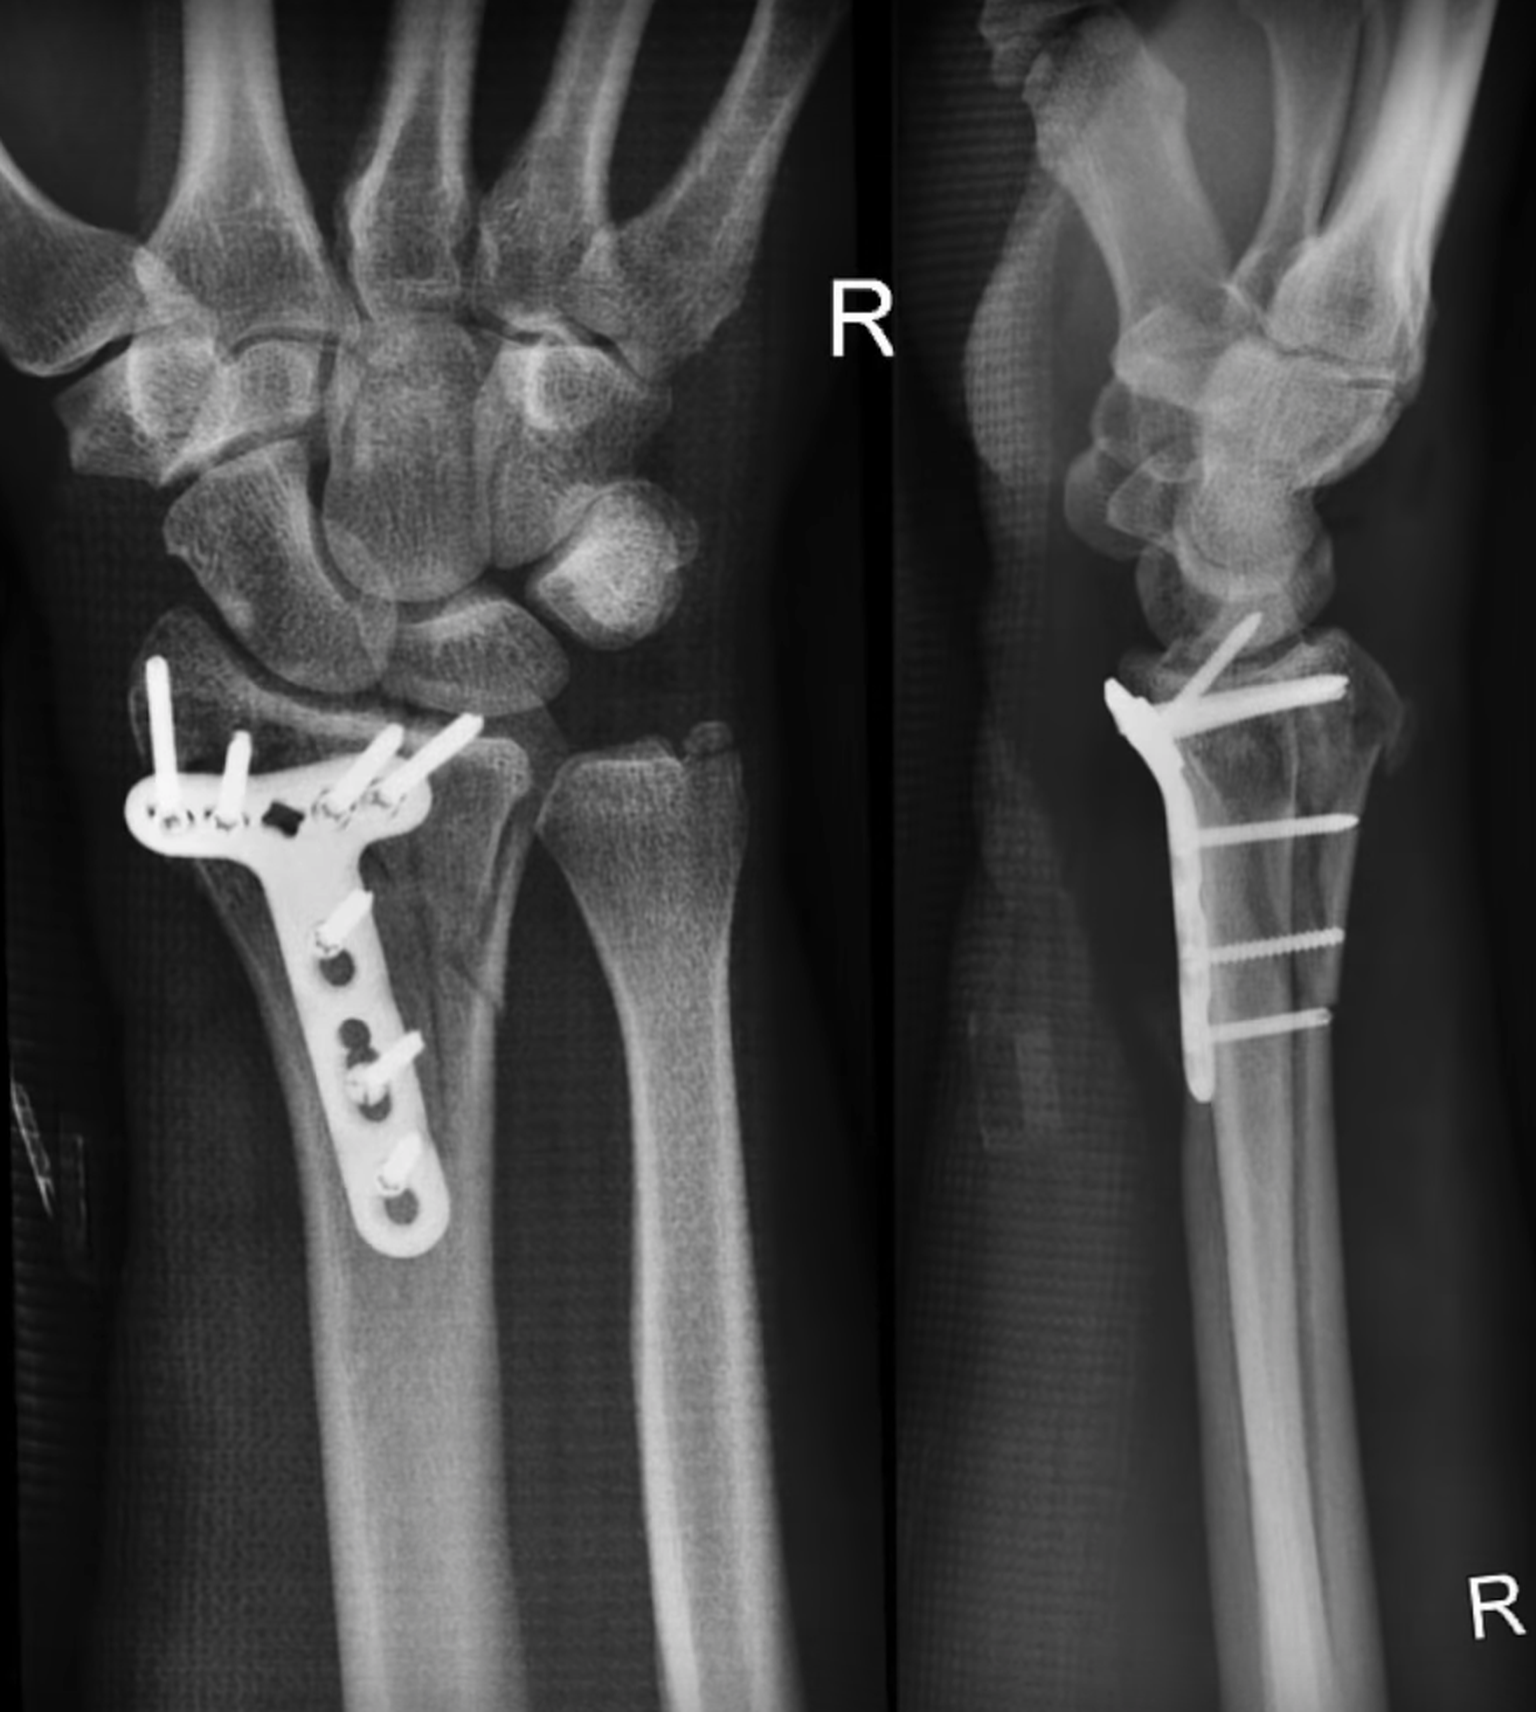

Nach der Operation: Gurskys Handgelenk.

Bild: youtube.com/Gursk3